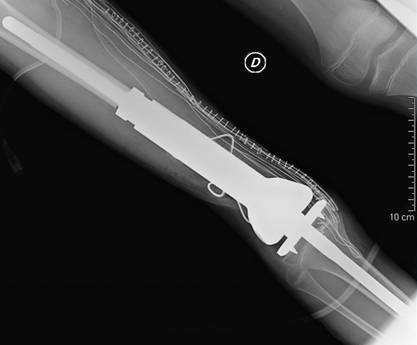

(ANSA) ROMA – Una protesi in titanio realizzata su misura e dotata di un dispositivo elettronico miniaturizzato è stata impiantata con successo per la prima volta nel Lazio in un bambino di 11 anni con un tumore che colpisce le ossa, l’osteosarcoma. La protesi intelligente ‘cresce’ con l’aumento di statura fisiologico del bambino, mantenendo così le due game della stessa lunghezza. La protesi è stata impiantata al femore della gamba destra, l’intervento, durato circa 5 ore, è stato condotto la scorsa settimana, da un’equipe di ortopedici e chirurghi vascolari guidata da Giulio Maccauro, responsabile dell’Unità operativa di Oncologia Ortopedica del Policlinico universitario Agostino Gemelli. In Italia sono state impiantate in tutto sette di queste protesi ‘smart’. La protesi si chiama ‘Mutars Xpand’ e, spiega Maccauro, “consente l’allungamento meccanico non invasivo dell’arto, attraverso una procedura eseguibile anche dal paziente o dai genitori istruiti dai medici”. Il modulo di allungamento di Mutars Xpand è costituito da un dispositivo elettronico miniaturizzato (attuatore) interno alla protesi, attivato tramite un ricevitore sottocutaneo da un’unità di controllo esterna gestita dal medico o dallo stesso paziente. Con Mutars Xpand si risolve il problema della lunghezza differente degli arti durante la crescita del bambino, senza ulteriori interventi chirurgici. Notevoli sono i vantaggi per il paziente rispetto alle altre soluzioni per il trattamento dei tumori ossei finora trattati con pratiche necessariamente demolitive o molto invasive. Mutars Xpand dà indubbi vantaggi anche rispetto alle protesi espandibili con meccanismo a vite oggi in uso.